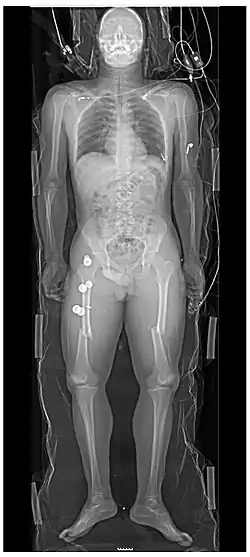

Extremities

A projectional radiograph of an extremity confers an effective dose of approximately 0.001 mSv, comparable to a background radiation equivalent time of 3 hours.[16]

- Hip joint: AP and Lateral.[15]

- The Lauenstein projection a form of examination of the hip joint emphasizing the relationship of the femur to the acetabulum. The knee of the affected leg is flexed, and the thigh is drawn up to nearly a right angle. This is also called the frog-leg position.

-

AP view of normal hip -

Lauenstein projection of normal hips

- Applications include X-ray of hip dysplasia.